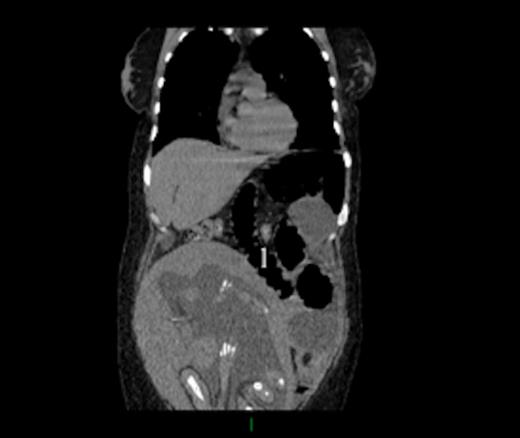

Six days after admission, a laparoscopic evaluation was performed but quickly converted into a laparotomy through a midline incision. An IH of the alimentary limb through the jejunojejunostomy mesenteric defect was found. The herniation was reduced and the strangulated part of alimentary limb was dusky but without frank ischemia. Petersen’s space and the jejuno-jejunostomy mesenteric defects were closed. Four days after surgery, the patient displayed with the same symptoms; a new CT scan (Fig 1) showed a volvulus of the jejunojejunal anastomosis. Re-laparotomy confirmed the CT scan diagnosis. The alimentary limb herniation was reduced and fixed; small bowel resection was not required. Fetal heart monitoring remained normal. Bowel function returned on the second postoperative day, and the remainder of the postoperative period was uneventful. She was discharged one week after second surgery.